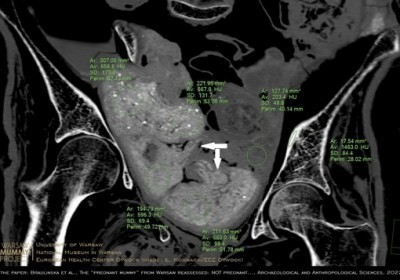

Płód znajdujący się w zmumifikowanej Egipcjance sprzed ponad dwóch tysięcy lat przetrwał do naszych czasów za sprawą bardzo nietypowego procesu rozkładu.…

Nie płód, ale kilka zawiniątek znajduje się w miednicy mumii kobiety prezentowanej w Muzeum Narodowym w Warszawie - dowodzi zespół naukowców. W jednym… Czytaj więcej